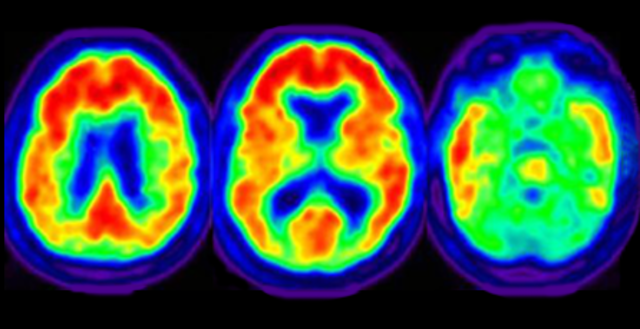

• First PET scan test

First PET scan test

The first PET scan was tested in the year 1878. The name stands for Positron Emission Tomography. Which is a picture of the inside of the brain showed as a tomography.